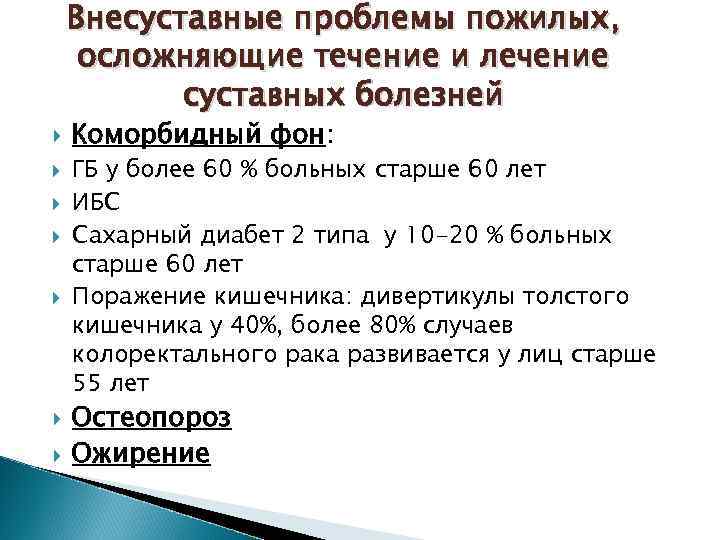

Внесуставные проблемы пожилых, осложняющие течение и лечение суставных болезней Коморбидный фон: ГБ у более 60 % больных старше 60 лет ИБС Сахарный диабет 2 типа у 10 -20 % больных старше 60 лет Поражение кишечника: дивертикулы толстого кишечника у 40%, более 80% случаев колоректального рака развивается у лиц старше 55 лет Остеопороз Ожирение